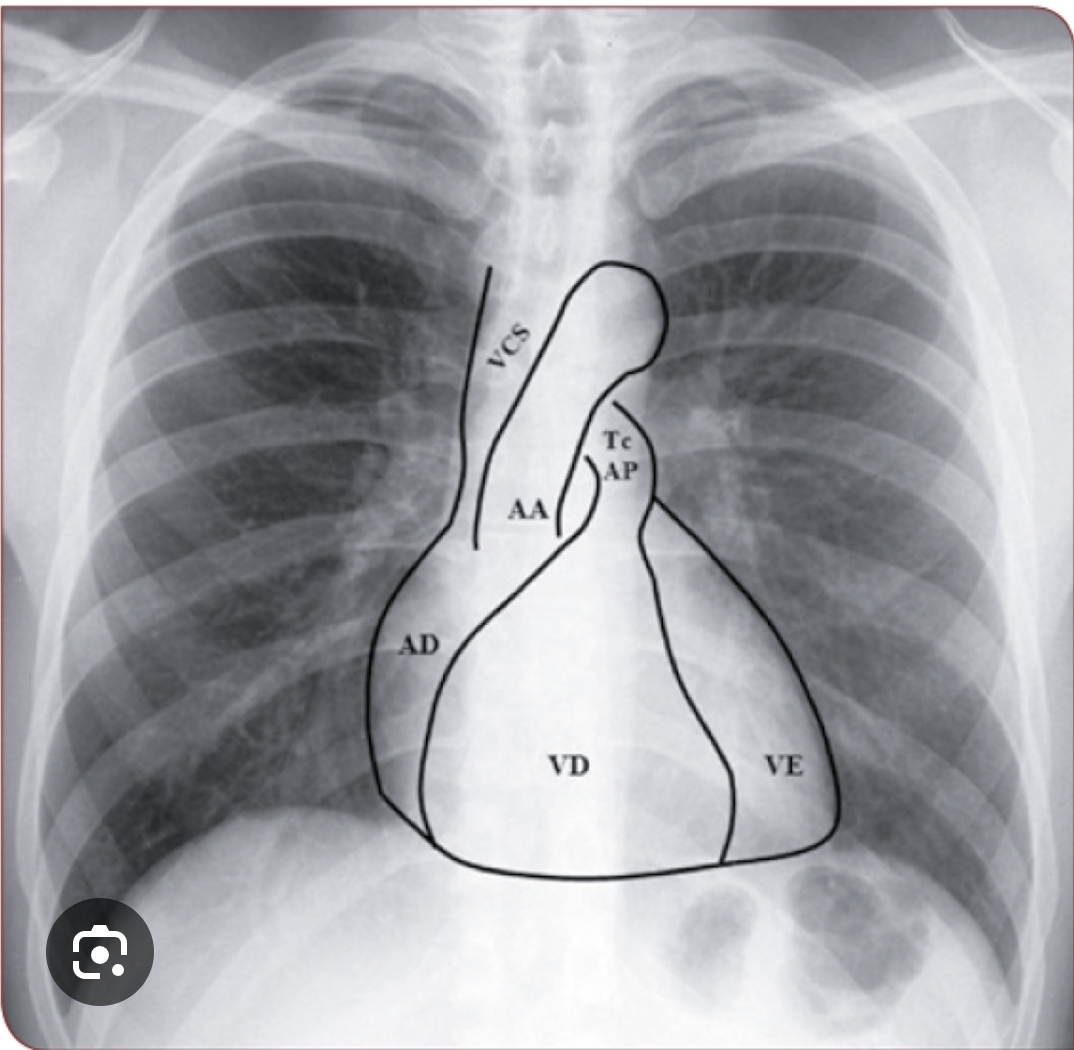

Anatomia cardíaca em PA?

A